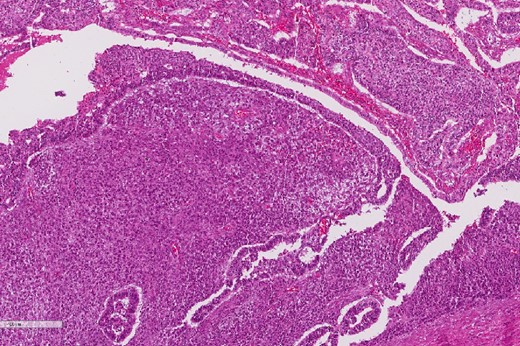

A review of the previously resected esophageal tumor revealed the presence of both epithelial and sarcomatous components. The epithelial component was composed of moderately to poorly differentiated adenocarcinoma, while the sarcomatous component showed hyperchromatic round to spindle cells with scant cytoplasm and frequent mitoses (Figs 3–6). The intrathoracic tumor showed a similar morphology as the sarcomatous component of the esophageal tumor, with focal rhabdomyoblastic differentiation (Fig. 7). The latter was strongly positive for desmin, myogenin, and MyoD1 and was focally positive for synoplastin, CD56, CD 10, and FL1.

The sarcomatous component of the esophageal tumor is formed of hyperchromatic round to spindle cells with scant cytoplasm and frequent mitoses.